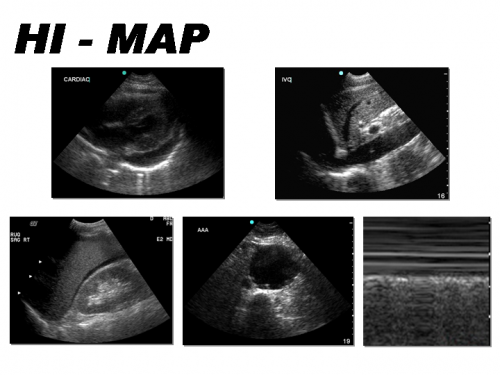

The Cardiac Views

The traditional cardiac view obtained as part of the FAST exam is the sub-xiphoid view. The main focus of this view in the FAST exam is to evaluate for evidence of cardiac injury by evaluating for pericardial effusion and/or cardiac tamponade. The probe is placed in the sub-xiphoid space medially, applying pressure to go under the xiphoid process and flattening out the probe while aiming caudally ('scooping out the heart')

The RUQ is the most sensitive region for free fluid in comparison to the other eFAST views.

The RUQ should be divided into 3 zones.

1. Above/Below the diaphragm,

2. Morrison’s pouch (hepato-renal recess)

3. Para-colic gutter: Around the inferior hepatic edge/inferior pole of kidney

The Left Upper Quadrant (LUQ)

The LUQ should also be divided into 3 zones:

1. Above/Below the diaphragm,

2. Spleno-Renal recess,

3. Paracolic gutter: Around the inferior pole of kidney

Lung Ultrasound

"Is there a pneumothorax?"

When using ultrasound to evaluate for a pneumothorax, the probe is usually placed on the anterior chest in the 2nd-4th intercostal space & midclaviular line.

The Suprapubic Views

The suprapubic view on the eFAST exam is generally the last of the four views performed.

Both Longitudinal & Transverse views are required